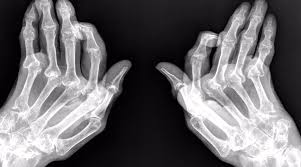

Para diagnosticar la artritis reumatoide, los médicos tienen en cuenta la historia médica, el examen físico, las radiografías y los estudios de laboratorio.